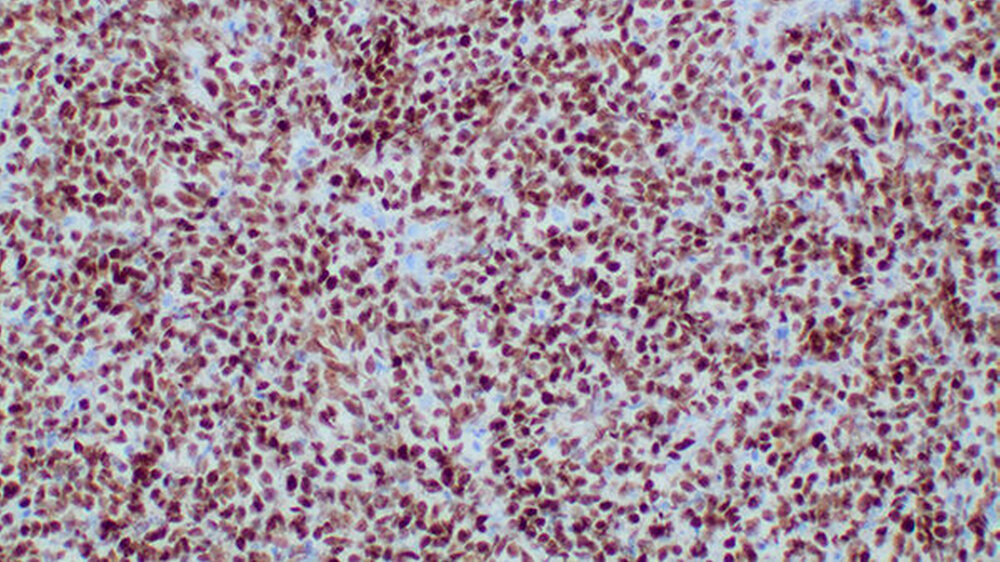

Der immunhistochemische Nachweis einer positiven Reaktion auf CD20 und c-myc (Abbildung 6) sowie die hohe Proliferationsfraktion (MIB-1) von über 90 Prozent führten zur Diagnose eines aggressiven Non-Hodgkin-Lymphoms der B-Zell-Reihe.

Durch in situ Hybridisierung wurde eine Expression des Epstein-Barr-Virus (EBV) ausgeschlossen. Somit konnte in der Zusammenschau aller Befunde die Diagnose eines Burkitt-Lymphoms gestellt werden. Der Patient wurde zur Induktion einer Chemotherapie in eine kinderonkologische Klinik verlegt.